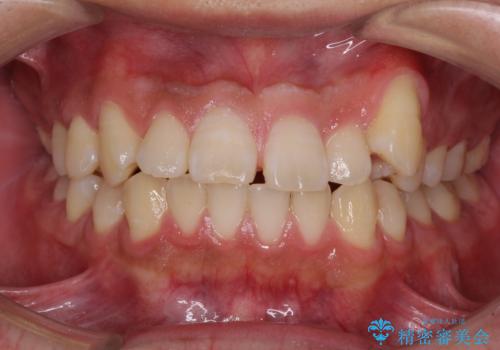

【ワイヤー矯正】八重歯 歯のでこぼこを治したい!

下顎前歯の叢生を短期間で改善

担当医 河口智英